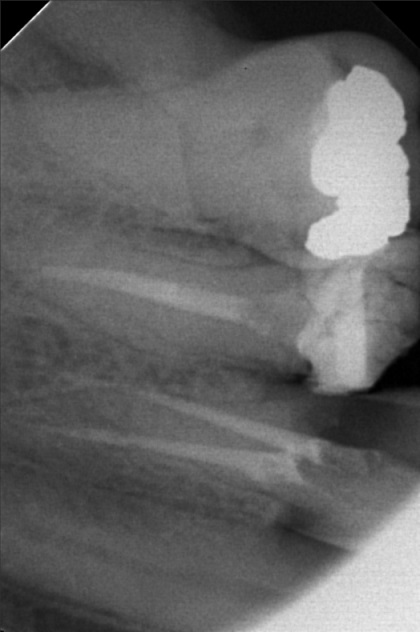

Edit Record Check our patient data records. Add patient information Patient Info Profile picture Last Name First Name Middle Name Birthdate Age Street Barangay City Country Zip Code Contact number Email Procedure > #25 buil-up w/fiber pero > 20mm obturation > xray > icf 09/03/22- open canal/ ML canal Eugenol/ Tf 9/10/10- MB #25 20mm, ML #30 20mm/ Camphenol, TF File sylvia_mariano.jpg File 2 sylvia_mariano_2.jpg File 3 sylvia_mariano_3.jpg File 4 sylvia_mariano_4.jpg File 5 File 6 File 7 File 8 File 9 File 10 File 11 File 12 File 13 File 14 File 15 File 16 File 17 File 18 File 19 File 20 Retain Record Retain Record Yes No Save Your Changes